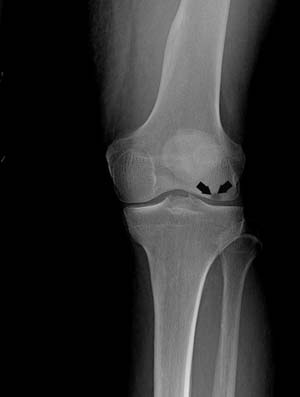

There are four stages of development of osteonecrosis of the knee which can be distinguished by symptoms and X-rays.

- Stage II : This stage follows in a couple of months and the X-rays will show flattened edges of the once rounded thighbones. An MRI, CT, or bone scan may be utilized to diagnose the condition.

- Stage III : At this stage, the condition becomes clearly visible on X-rays and no other diagnostic tests are required. At this point the bone, itself, begins to decay away, and cartilage covering the bones loosens from other segments of the leg. Surgical treatments are considered at this stage.

- Stage IV : In this stage, the bone collapses, joint space narrows, bone spurs form, and the articular cartilage is destroyed. The only treatment at this point is joint replacement surgery.